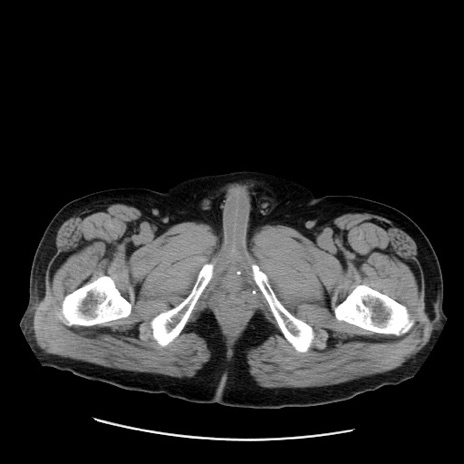

症例20(横断像)

【症例】 60歳代男性

【主訴】 腹部膨満、嘔吐

【現病歴】5日前頃より倦怠感を認め食事量減少し4日前の朝嘔吐、食事摂取困難となった。 3日前近医受診し点滴施行され整腸剤などを処方された。 当日他院を受診し、腹部膨満著明、炎症反応の上昇(CRP10.8、WBC11200)あり、紹介受診となる。

【身体所見】 意識JCS1 受け答えがはっきりしないBP 111/57mHg、 P 67bpm、、BT35.2°C、SpO2 97%(RA)、 腹部:膨隆、打診で鼓音あり、全体的に圧痛有り、腸蠕動音(-)、反跳痛ははっきりせず。

【データ】WBC 11400、CRP 14.20